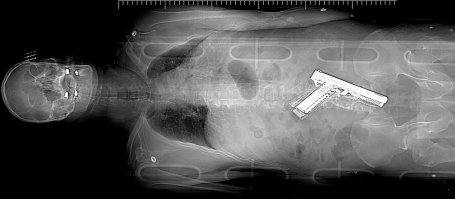

CONSIDER OTHER POTENTIAL SOURCES OF INJURY

When evaluating a patient brought to you from a tactical scene, keep your mind that there are numerous ways someone can be injured: fragmentation (grenades, explosives), burns (flash bangs), chemical (pepper spray or hazmat), lacerations from broken glass, blunt trauma (restraint, impact weapons, falls), taser barbs, heat/cold illness, dehydration.